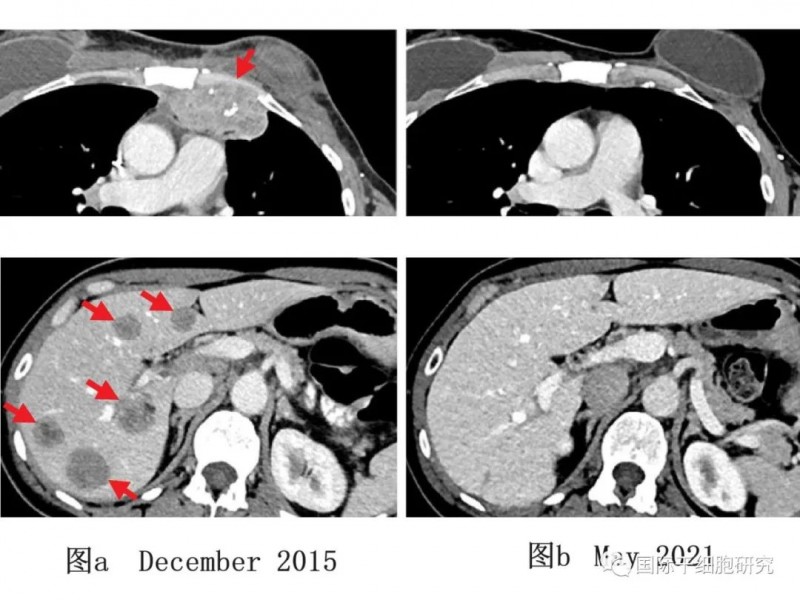

图2 一例乳腺癌患者TILs治疗前后影像学对比

图a:该例乳腺癌患者治疗前(2015年12月)的影像学检查,示患者胸壁(上,左)和肝脏(下,左)处,有转移性病变。

图b:该例乳腺癌患者在接受免疫治疗后(2021年5月)的影像学检查,示患者肿瘤完全缩小,随访5年未见新发癌症。